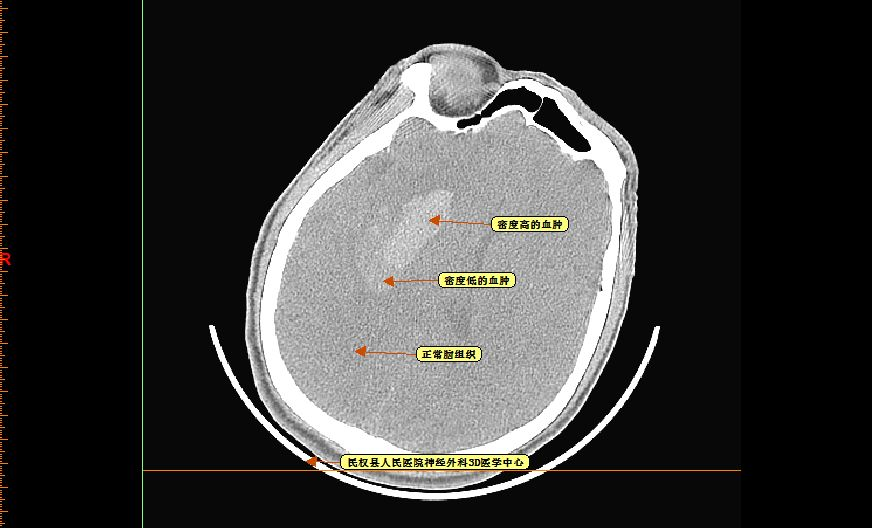

再仔细观察并划定血肿分层区域,可设定血肿为高密度区域、低密度区域,和正常脑组织对比

以红色区域划分为高密度区域、蓝色区域划分为低密度区域

测量各密度区域CT阈值,可见高密度区域(红色区域)CT阈值为60.66,低密度区域(蓝色区域)CT阈值为44.39,正常脑组织区域CT阈值为20.94。

应用3D重建,CT域值设定在55-100,重建血肿量为16.7ml。

把CT阈值设定为44--100重建血肿量为24.87ml(此血肿量包括分层的高密度血肿及低密度血肿)。

剖开24.87ml血肿看看血肿的分层情况,绿色的为CT阈值设定为55--100时高密度的血肿,红色的为CT阈值设定为44--100时增加的分层低密度血肿。

因为病人意识呈进行性加重、头痛较入院时明显,虽然血肿量为24.87ml,但三脑室受压明显,血肿周围的低密度(上图红色的部分)通过两次CT对比考虑为血肿周围析出的血清部分或长期饮酒造成的特殊血肿形态--分层结构,排除活动性出血;因其长期饮酒,担心其开颅术中止血困难,与家属在3D下沟通后拟行微创穿刺置管引流术。